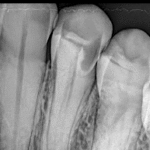

Dental cavity is a most common dental disease. Millions of people in all ages affected by dental cavity. …